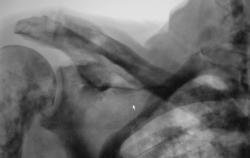

Метастазы в костях основания черепа.

Женщина средних лет с клиникой невралгии тройничного нерва справа. На КТ были выявлены округлые очаги деструкции в костях основания черепа (средней черепной ямки).

Наблюдение Nela.